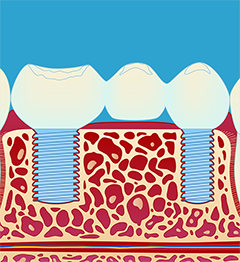

Hva er et implantat?

Tannimplantater brukes til erstatning av manglende tenner. De opereres inn i kjevebenet. Når benet har grodd rundt implantatene, blir selve tannerstatningen laget. I tilfeller der flere tenner mangler, er det mulig å operere inn to eller flere implantater og lage en implantatbro. Behandlingen er en prosess som strekker seg over flere tannlegebesøk og krever grundige forundersøkelser og nøye planlegging. Moderne implantatbehandling er sikker og trygg behandling med god prognose og holdbarhet.

1.) Innsetting av implantat (fikstur) (fig. I-II). Operasjonen utføres under lokalbedøvelse. Etter inngrepet vil man motta mer utfyllende informasjon. Slik vet man hvordan man skal forholde seg i tiden etter operasjonen.

3.) Fremstilling og montering av kronen (fig III-V). Det er en tanntekniker som lager selve broen. Broen blir vanligvis festet med små skruer, slik at den senere kan tas av ved behov. Dette krever vanligvis 2 eller flere tannlegebesøk.

- En tannerstatning festet til implantater fungerer for de fleste pasienter som egne tenner, og den synlige delen av erstatningen ser ut som naturlige tenner. Et tannimplantat har likevel ikke samme form som en tannrot, og det kan det være vanskelig å gi overgangen mellom implantat og krone et naturlig utseende.